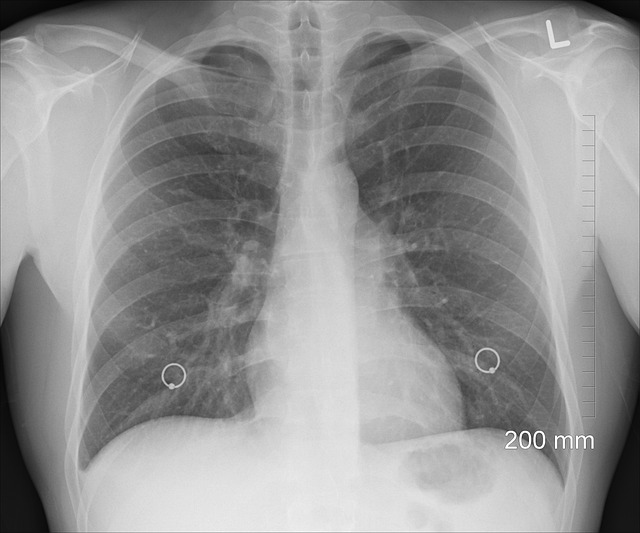

๋น์์ธํฌ์ฑ ํ์์ด๋?

๋น์์ธํฌ์ฑ ํ์์ ํฌ๊ฒ ์ธ ๊ฐ์ง ์ํ์ผ๋ก ๋๋ ์ ์์ต๋๋ค.

- ์ ์ (Adenocarcinoma): ๊ฐ์ฅ ํํ ํํ๋ก, ์ ์ฒด ๋น์์ธํฌ์ฑ ํ์์ ์ฝ 50% ์ด์์ ์ฐจ์งํฉ๋๋ค. ๋นํก์ฐ์์๊ฒ๋ ๋ฐ์ํ ์ ์์ผ๋ฉฐ, ์ฃผ๋ก ํ์ ๋ฐ๊นฅ์ชฝ ๋ง์ด๋ถ์์์ ๋ฐ์ํฉ๋๋ค.

- ํธํ์ํผ์ธํฌ์ (Squamous Cell Carcinoma): ํก์ฐ์์๊ฒ ๋ง์ด ๋ํ๋๋ฉฐ, ํ ์ค์ฌ๋ถ์์ ๋ฐ์ํ๋ ๊ฒฝ์ฐ๊ฐ ๋ง์ต๋๋ค.

- ๋์ธํฌ์ (Large Cell Carcinoma): ๋๋ฌผ์ง๋ง ์ฑ์ฅ ์๋๊ฐ ๋น ๋ฅด๊ณ , ์ ์ด ์ํ์ด ๋์ ํน์ง์ ๊ฐ์ง๋๋ค.

์ธ ์ํ์ ์น๋ฃ ์ ๋ต์ด๋ ์ํ์ ์์ด ์ฐจ์ด๊ฐ ์๊ธฐ ๋๋ฌธ์ ์กฐ์ง๊ฒ์ฌ ๋ฐ ๋ถ์์ง๋จ์ ํตํด ์ ํํ ์ ํ์ ํ์ ํ๋ ๊ฒ์ด ํ์์ ๋๋ค.

๋น์์ธํฌ์ฑ ํ์์ ์ด๊ธฐ์๋ ๋๋ ทํ ์ฆ์์ด ๊ฑฐ์ ์์ต๋๋ค. ์ฆ์์ด ๋ํ๋ ๋๋ ์ด๋ฏธ ์๋น ๋ถ๋ถ ๋ณ์ด ์งํ๋ ๊ฒฝ์ฐ๊ฐ ๋ง๊ธฐ ๋๋ฌธ์, ์ฃผ๊ธฐ์ ์ธ ๊ฒ์ง์ด ์ค์ํฉ๋๋ค.